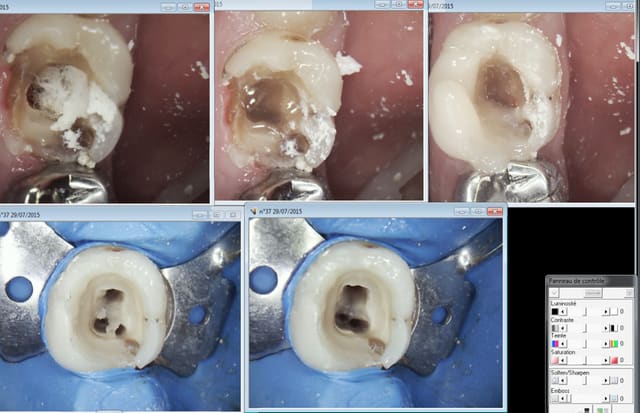

Par contre j'ai essayé le clip flow pour protéger l'entrée des canaux lors de la réalisation pré endo ( endo en 2 temps because urgence) autant ca marche bien pour les onlays autant c'est la galère à virer dans ce cas. -)))))

C'est à moitié mou le r25 passe à travers heureusement ! -))))

Ta reconstitution pré endo tu l'as fait avec quel compo sur les 3 que tu montres ?

Moi la dernière fois j'ai utilisé un compo flow quelconque pas cher mais j’osai pas trop remonté donc mon crampon tenait pas et quand j'ai rajouté ça a pété !

C'est la meme.

J'ai utilisé le peak universal bond ( coltène) seul ( sans etching en plus !) puis estelite flow quick pour la base et estelite posterior pour monter les parois. C'est le collage qui cède pas le compo tu fais ca avec un SAM 1 ca pète, pour te donner le niveau d'adhésion de ces merdes. -)))

je le fait aussi tout en flow quand c'est pas trop abimé comme ci dessus, le flow c'est moins pratique quand c'est trop délabré. Et ca ne saute pas facilement. -))))